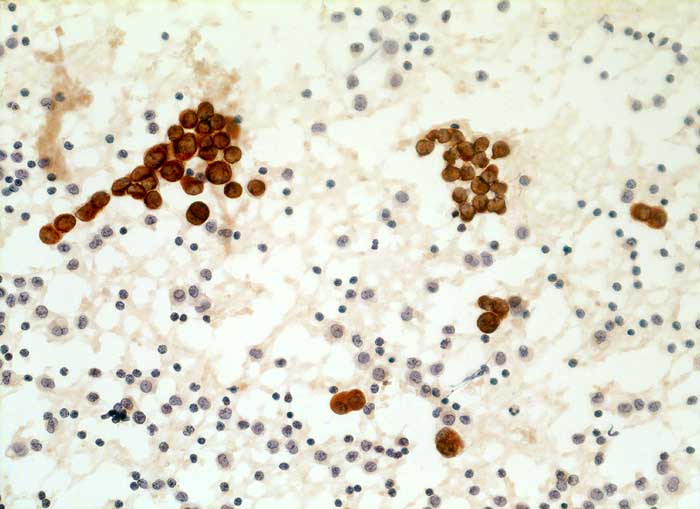

Aszitespunktat: Die Mesothelzellen sind positiv für den Panzytokeratinmarker Lu-5. Die Entzündungszellen sind Lu-5 negativ.

Immunzytochemisch reagieren erwartungsgemäss die Mesothelien deutlich mit dem panepithelialen Antikörper Lu-5. Mit dem epithelialen Marker Ber-EP4 stellen sich jedoch keine Zellen dar. Dies spricht gegen das Vorliegen eines Karzinoms.

Kommentar: Leicht abnorme Mesothelverbände oder Makrophagenaggregate sind typisch für Ergüsse bei Lebererkrankung. Die Differentialdiangose gegenüber einem Karzinom ist manchmal schwierig. Da BerEp-4 in ca. 90% aller Karzinome positiv ist, Mesothelien aber nicht mit dem Marker reagieren, ist dieser Marker eine wertvolle Hilfe. Die Mesothelzellverbände sind dagegen für Lu-5 und polyklonales Keratin positiv und nicht zur Differenzierung von Mesothelien und Karzinomzellen geeignet.

Zytologie

Immunhistochemie

Lu5 Panzytokeratin

200